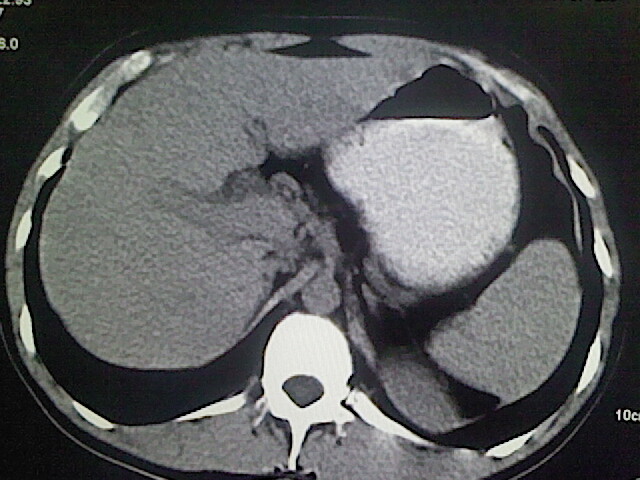

以下是引用卜一在2009-3-14 9:49:00的发言:[br]胆囊萎缩,胆囊壁不规则增厚,内部结构模糊,增强明显强化。另:肝左叶外侧段肝囊肿。支持:慢性胆囊炎!高度可疑:胆囊癌!

以下是引用余辉在2009-3-14 8:48:00的发言:[br]1)慢性胆囊炎。2)肝左叶外侧段肝囊肿。3)脂肪肝。[br]支持,胆囊萎缩,密度增高,不知b超具体有何提示,钙胆汁?结石?

以下是引用jiangjing在2009-3-14 10:18:00的发言:[br]1)慢性胆囊炎。2)肝左叶外侧段肝囊肿。3)脂肪肝。4.】建议行肝功能检查